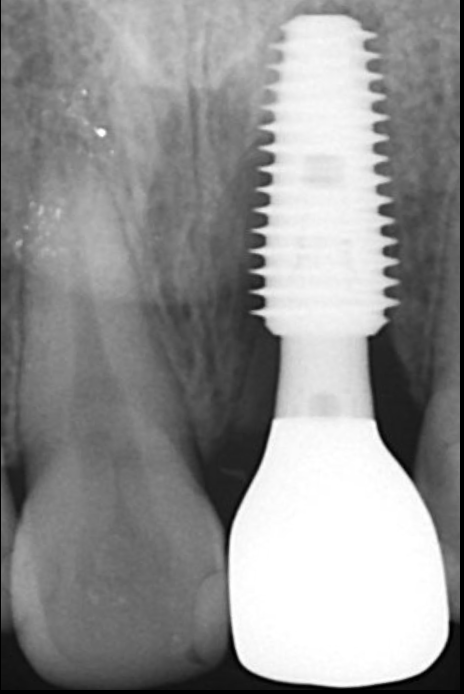

初診時の口腔内写真とデンタルX線写真

インプラントSET後の口腔内写真とデンタルX線写真